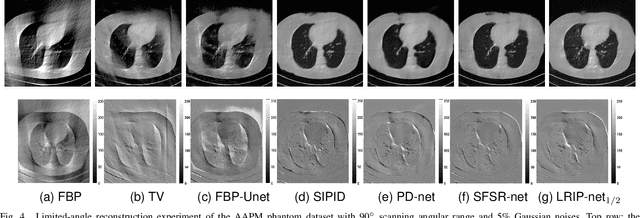

Abstract:In the practical applications of computed tomography imaging, the projection data may be acquired within a limited-angle range and corrupted by noises due to the limitation of scanning conditions. The noisy incomplete projection data results in the ill-posedness of the inverse problems. In this work, we theoretically verify that the low-resolution reconstruction problem has better numerical stability than the high-resolution problem. In what follows, a novel low-resolution image prior based CT reconstruction model is proposed to make use of the low-resolution image to improve the reconstruction quality. More specifically, we build up a low-resolution reconstruction problem on the down-sampled projection data, and use the reconstructed low-resolution image as prior knowledge for the original limited-angle CT problem. We solve the constrained minimization problem by the alternating direction method with all subproblems approximated by the convolutional neural networks. Numerical experiments demonstrate that our double-resolution network outperforms both the variational method and popular learning-based reconstruction methods on noisy limited-angle reconstruction problems.